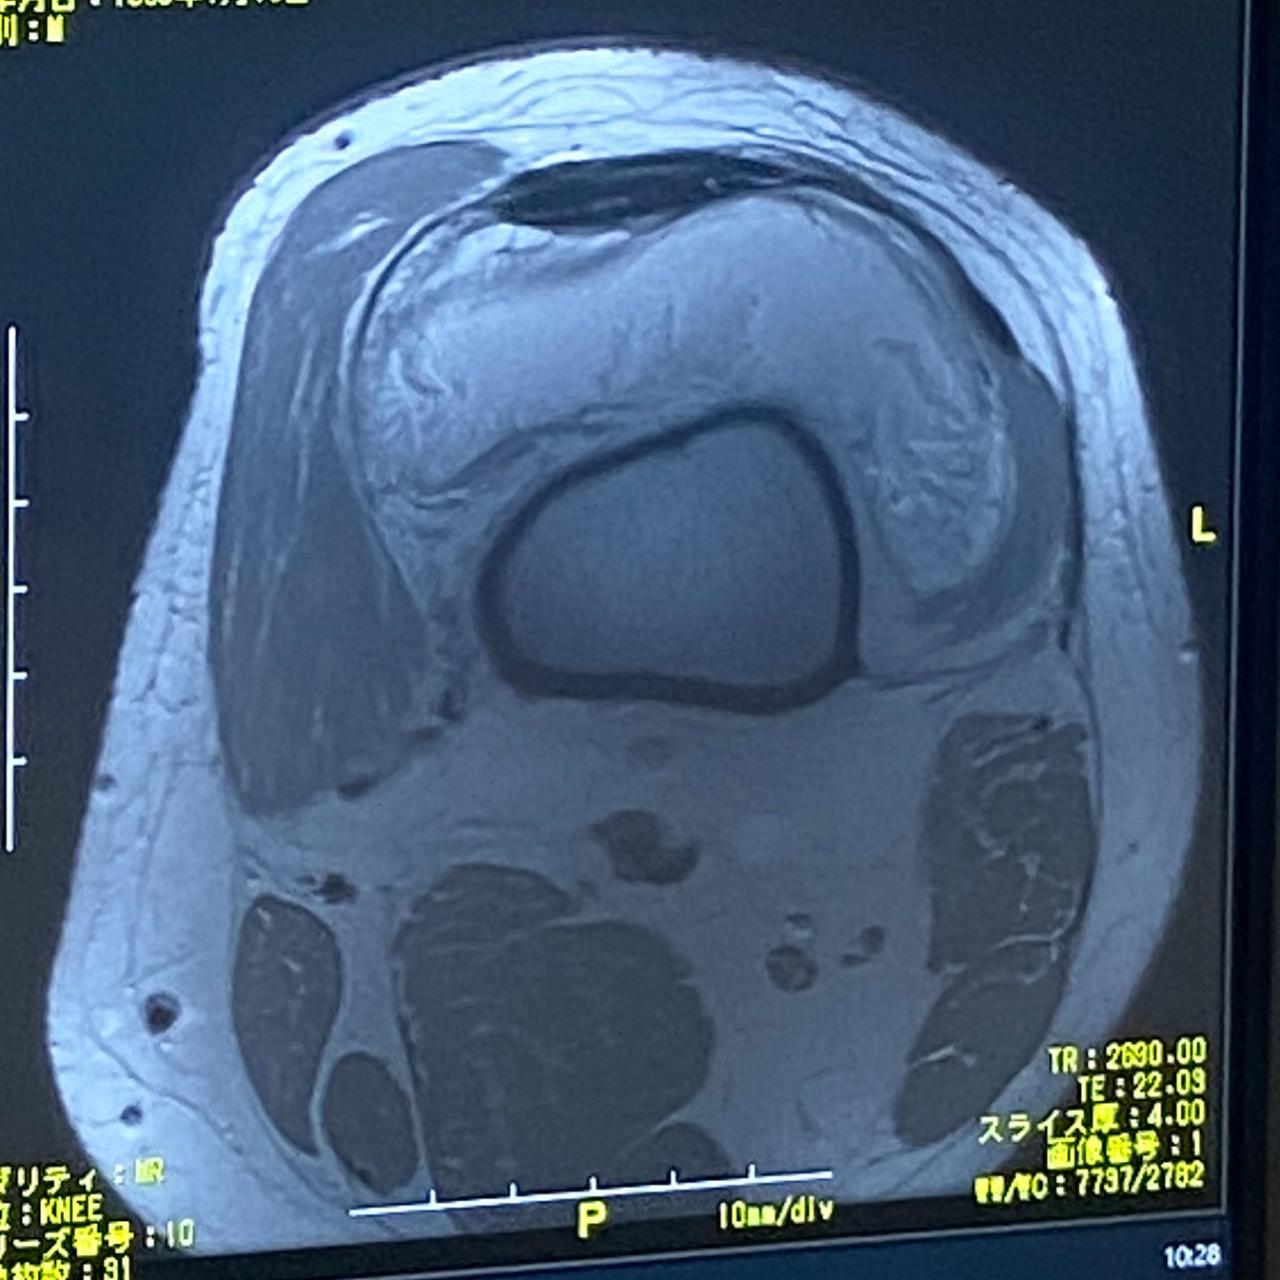

膝がぶっ壊れましたねw

しかも10年前ぐらいにホッケー中に痛めた膝

ずっと筋肉系の痛みかと思ったら

骨が変形してましたw

笑いごとじゃないんですが

水も溜まって散々ですw

はやく病院行っとけばよかったwww